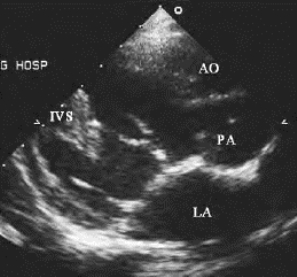

图17-3 右室双出口二维超声图

胸骨旁心脏长轴切面,显示主动脉及肺动脉均发自右心室、并显示室间隔缺损